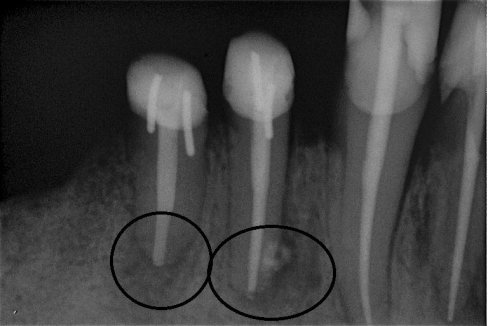

Fallbeispiel für eine unvollständige Wurzelfüllung

nach Revision und dichtem Verschluss

Im ersten Schritt wird nach der Eröffnung des Zahnes die alte Wurzelfüllung entfernt und es erfolgt die Reinigung des gesamten Systems. Nach dem Reinigen wird für einige Zeit ein desinfizierend und gewebsauflösendes Medikament in den Zahn eingebracht, welches die Desinfektion auch in schwierig erreichbaren Nebenbereichen des Kanalsystems unterstützt.

Sind Reinigung und Desinfektion des Zahnes abgeschlossen, werden die sauberen Kanäle mit der thermoplastischen Obturation 3-dimensional verschlossen. Auch die kleinen Seitenkanäle können so verschlossen werden.